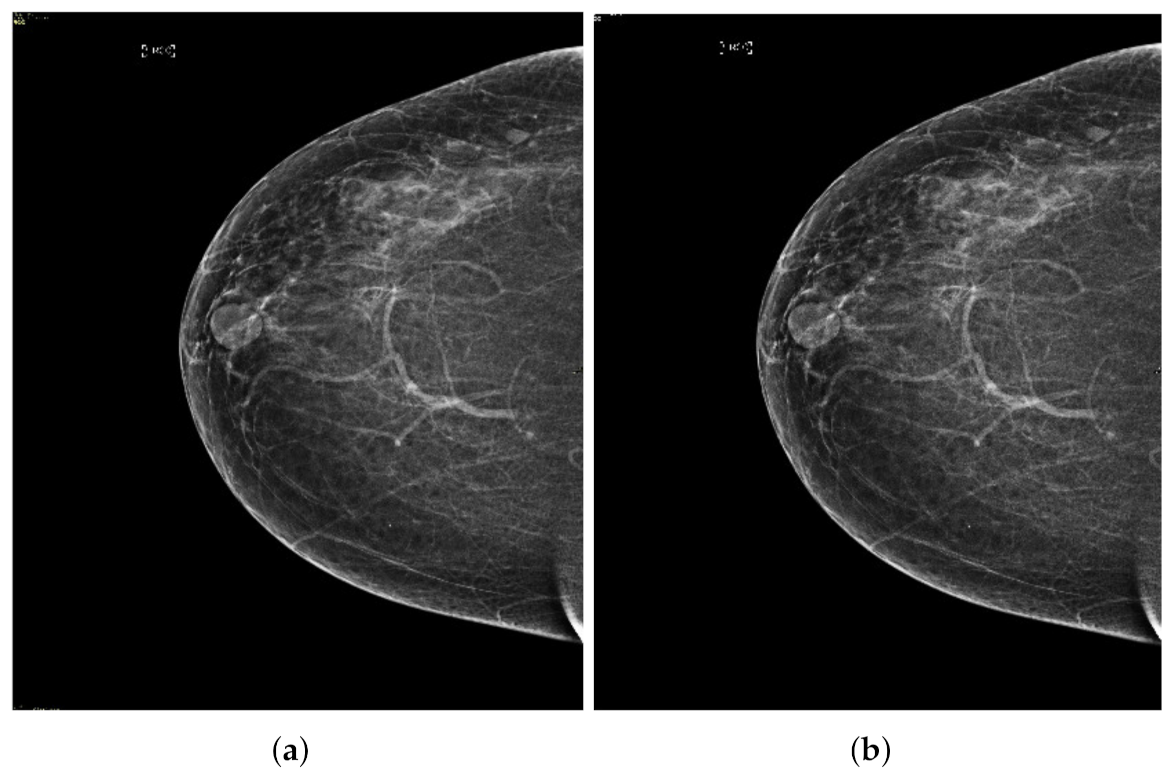

Mammographic image coherency contains two steps, the first step is based on the second-order Gaussian Laplacian (LoG) to normalize the set of mammography images as the output is shown in Figure 6. Although some regions, especially the regions containing a breast mass, the pixels are low intensities. These low pixels areas are not observed correctly, making it difficult to segment the cancerous area. We used oriented diffusion filtering as a second step to obtain a well-normalized image.

Figure 6.

Mammogram coherent images. (a) Second order Laplacian of Gaussian output image and (b) anisotropic oriented diffusion filter image.

The more coherent images lead to more precise segmentation of the cancerous region from the mammography images. We apply the oriented diffusion filter [46] for coherent areas of low contrast region, as it is a suitable filtering method for normalized regions with low contrast. The oriented diffusion filter requires the recomputed orientation data of the image in advance, and this orientation data is called the orientation field (OF). The orientation field makes the diffusion tensor with the flow of the pixels of the image. The primary motivation for using an anisotropic diffusion procedure is based on the tilt angle of the best ellipse. It is achieved through the Second Order Gaussian detector, which gives the right direction for the low contrast region. The diffusion procedure is defined as follows:

The diffusion process is an iterative algorithm that processes the pixels from the initial mammography images to develop a smoother structure with each step [47]. The fine structure is achieved with a normalized image; there should be an appropriate stop criterion to get a fine structure. The stopping criterion is introduced in recent research works. The stop iteration process of the stop criterion is based on the rate of change of the spatial entropy value of the image relative to the number of iterations. The Figure 6a shows the output of the anisotropic oriented diffusion filter, and the output of the second-order Gaussian filter is also shown in the Figure 6b. It observed that this anisotropic oriented diffusion filter gives more coherence to the images in particular area, especially the area of the breast concerning the background compared to the Gaussian second order filter.